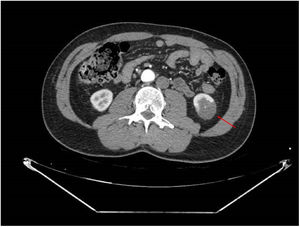

Se realizó angioTC de abdomen y pelvis (figs. 1 y 2), en el que se observó un infarto del polo inferior renal izquierdo (15% del parénquima renal), con una disminución del calibre de una de las ramas segmentarias de la arteria renal izquierda. Este hallazgo fue sugerente de disección espontánea de una rama inferior de la arteria renal izquierda, aunque al presentar pequeñas placas dispersas de ateromatosis calcificadas a nivel de arteria aorta abdominal no podía descartarse etiología embolígena o una lesión de la arteria renal subyacente.